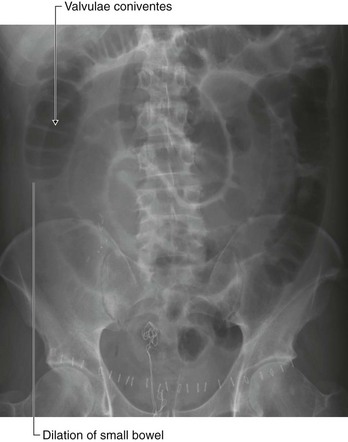

Peritoneal spread of disease

The large surface area of the peritoneal cavity allows infection and malignant disease to spread easily throughout the abdomen (Fig. 4.55). If malignant cells enter the peritoneal cavity by direct invasion (e.g., from colon or ovarian cancer) spread may be rapid. Similarly, a surgeon excising a malignant tumor and releasing malignant cells into the peritoneal cavity may cause an appreciable worsening of the patient’s prognosis. Infection can also spread across the large surface area.

image

Fig. 4.55 Peritoneal metastasis on the surface of the liver. Computed tomogram in the axial plane of the upper abdomen.

The peritoneal cavity can also act as a barrier to, and container of, disease. Intra-abdominal infection therefore tends to remain below the diaphragm rather than spread into other body cavities.

A perforated bowel (e.g., caused by a perforated duodenal ulcer) often leads to the release of gas into the peritoneal cavity. This peritoneal gas can be easily visualized on an erect chest radiograph—gas can be demonstrated in extremely small amounts beneath the diaphragm. A patient with severe abdominal pain and subdiaphragmatic gas needs a laparotomy.